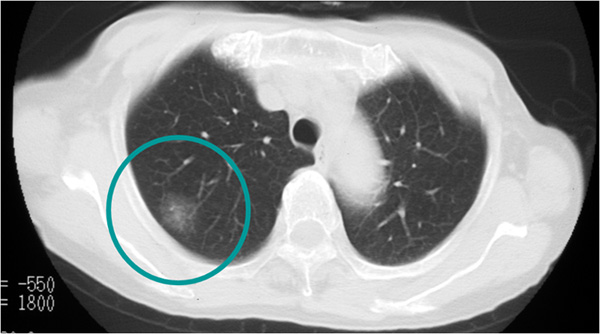

近年、胸部CTで「すりガラス陰影(ground-glass opacity: GGO, ground-glass nodule: GGN)」を呈する腺がん症例が増加しています。肺の末梢部に発生しやすい肺がんで、近年増えてきて肺がん全体の60%程度を占めるようになっており、特に非喫煙者の女性に多い組織型です。

肺腺がん 胸部CT所見

末梢型小型肺腺がんに対しては、予後を考慮した野口分類が日本では広く使われてきて、現在も一部で用いられています。野口Type A, Type Bは早期肺がん例であり、切除後は良好な予後が期待されます。

すりガラス陰影(ground-glass opacity: GGO)を呈する肺腺がん 胸部CT所見